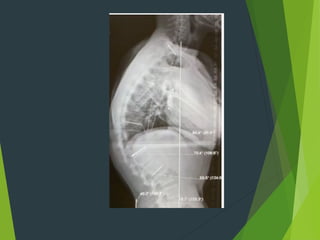

X-ray : wedging and fragmentation of the

upper

and lower vertebral end plate .

Patient presented withsmooth , rigid kyphosis of the dorsal spine with back pain ; the disease affecting the adolescent . X-ray : wedging and fragmentation of the upper and lower vertebral end plate . Treatment : Exercise and some time we use brace or splint .